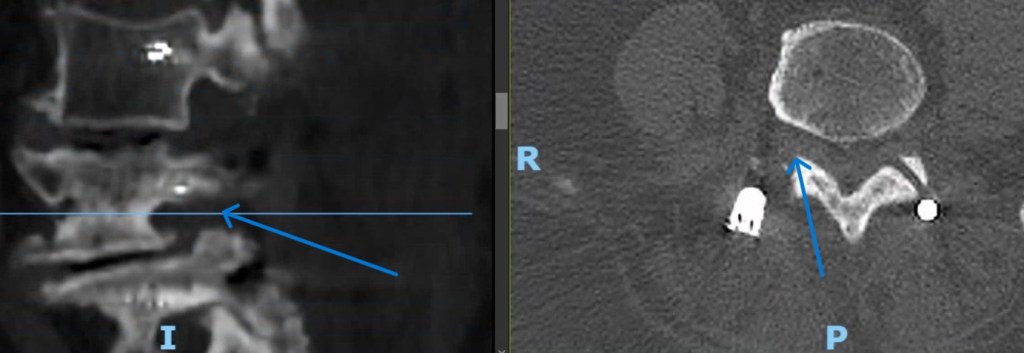

-Hernia discal dorsal: Mucho menos frecuentes que las hernias discales lumbares y cervicales. Asocian generalmente dorsalgia no irridiada. La mayoría mejora con tratamiento conservador. Sin embargo, en caso de que generen compresión a nivel de la médula espinal pueden dar lugar a un cuadro de mielopatía con ataxia de la marcha y paraparesia espástica precisando intervención quirúrgica.

–Fracturas vertebrales: Frecuentes sobre todo en la columna dorso-lumbar, pueden aparecer como consecuencia de mecanismos muy diversos; desde grandes traumatismos, en cuyo caso su tratamiento puede estar condicionado por la presencia de otras lesiones, o bien tras traumatismos banales o incluso de forma espontánea, sin traumatismo alguno. Estos últimos casos definen las «fracturas patológicas» en las que es preciso buscar una causa subyacente estructural o sistémica que haya provocado el debilitamiento óseo. Esta situación es especialmente frecuente en mujeres tras la menopausia debido al desarrollo de osteoporosis. Estos casos precisan iniciar un tratamiento para compensar la desmineralizacón ósea. El tratamiento de las fracturas depende fundamentalmente del grado de deformidad asociado, la afectación de ligamentos (ambos aspectos definen la presencia o no de inestabilidad) y el que exista o no una lesión neurológica. En caso de fracturas estables sin déficit neurológico se emplea una ortesis mientras que en presencia de inestabilidad o afectación neurológica debe valorarse la cirugía.